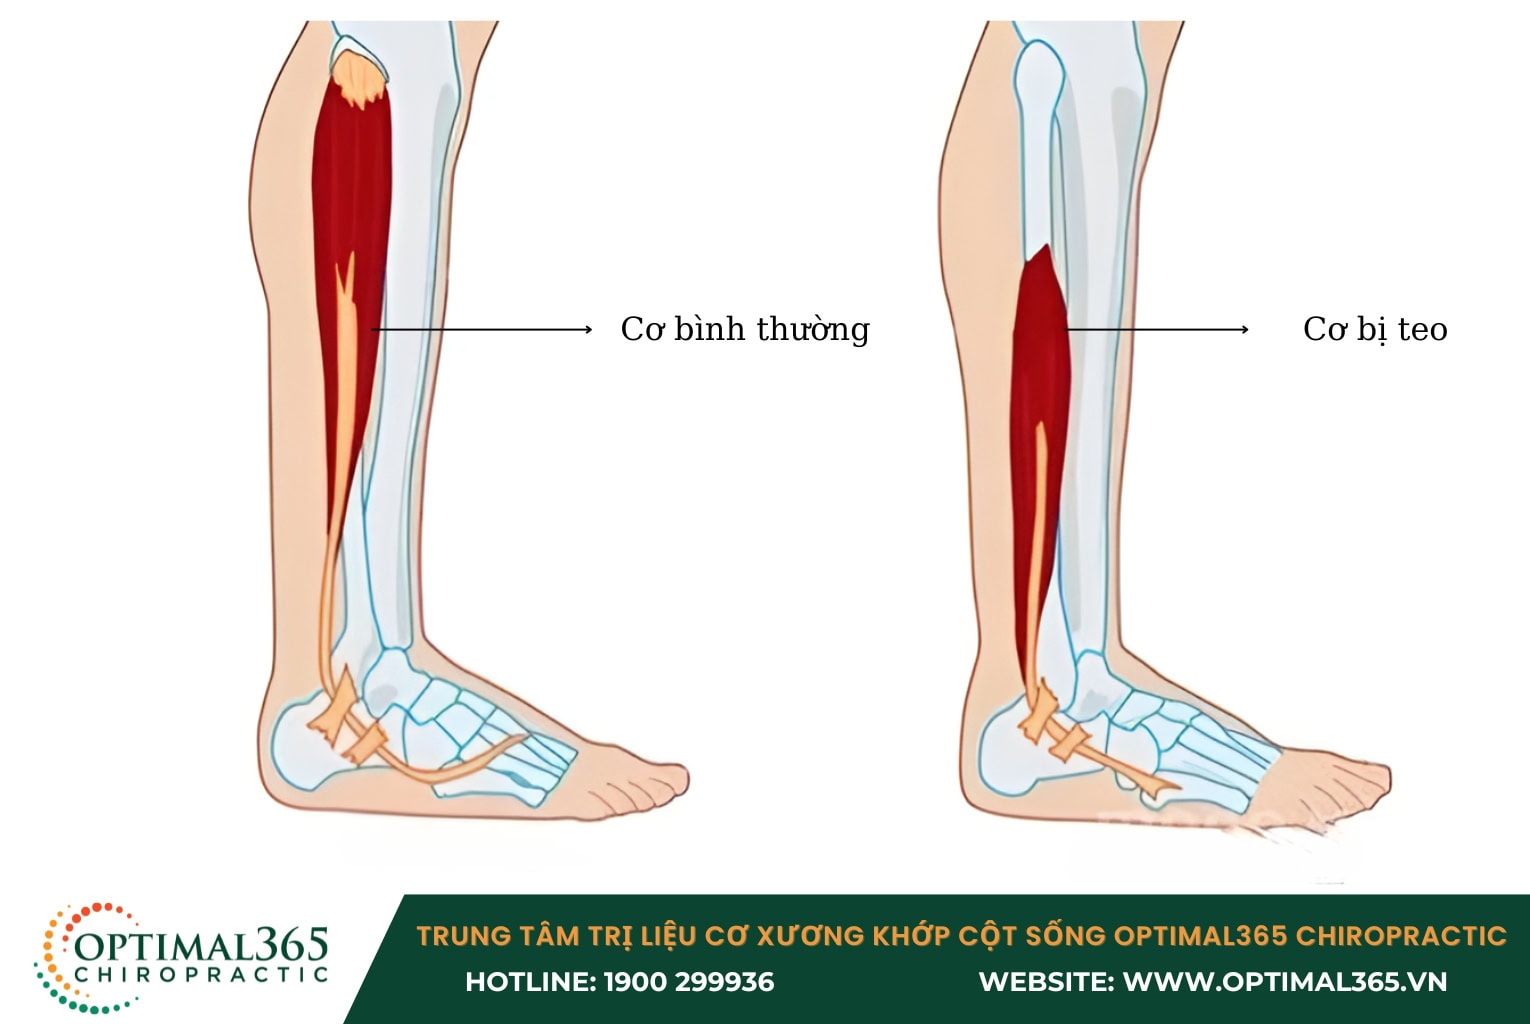

- Teo cơ xung quanh gối, dẫn đến sự yếu dần của khớp.

- Teo cơ đùi: Sau một thời gian, cơ đùi ở bên chân bị chấn thương có thể bị teo nhỏ so với bên lành, làm tăng áp lực lên chân lành, lâu dần có thể gây tổn thương cho chân này.